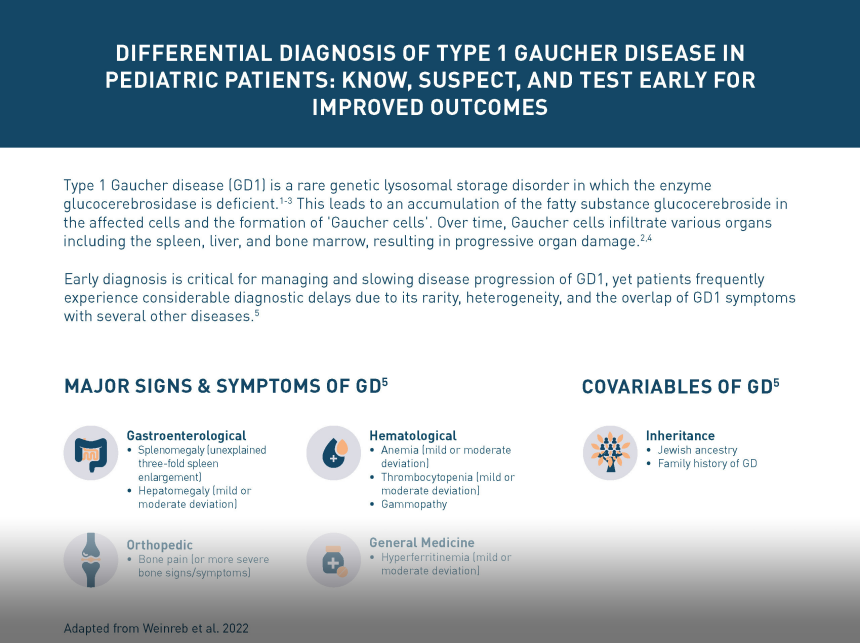

The age of onset and the severity of symptoms of type 1 Gaucher disease (GD1) can vary considerably.1,2 The main clinical manifestations include:

Visceral

Splenomegaly occurs in 95% of patients with GD1. It may be one of the first and most physically prominent presentations of GD1 in patients. Splenomegaly results in abdominal distension and early satiety.4–7 Many patients complain of acute abdominal pain, which can be worsened by splenic infarction.1,8

Enlargement of the liver occurs in 80% of patients with GD1, also contributing to abdominal pain and early satiety.1,5,7 Hepatomegaly may progress to liver disease and cirrhosis.1,4

Hematological

Bruising, bleeding, and nosebleeds occur due to thrombocytopenia.1,4,6

Fatigue is common, occurring in 50% of patients with GD1.6,7

Gammopathy can be polyclonal or monoclonal, and is detected very often in patients.9,10 This can lead to long-term hematological complications.9

Hyperferritinemia is very often detected in patients and can contribute to long-term hematological complications.10

Long-term hematological complications include a risk of developing hematological malignancies and solid tumors.10,11

Skeletal

Skeletal involvement occurs in 70–100% of patients with GD1 and includes abnormal bone shaping, bone pain, bone infections, and fractures.5 Skeletal manifestations are associated with considerable pain, limitations in mobility, and a significantly reduced quality of life.11,12 In severe cases, they can lead to potentially irreversible complications or long-term disability.13